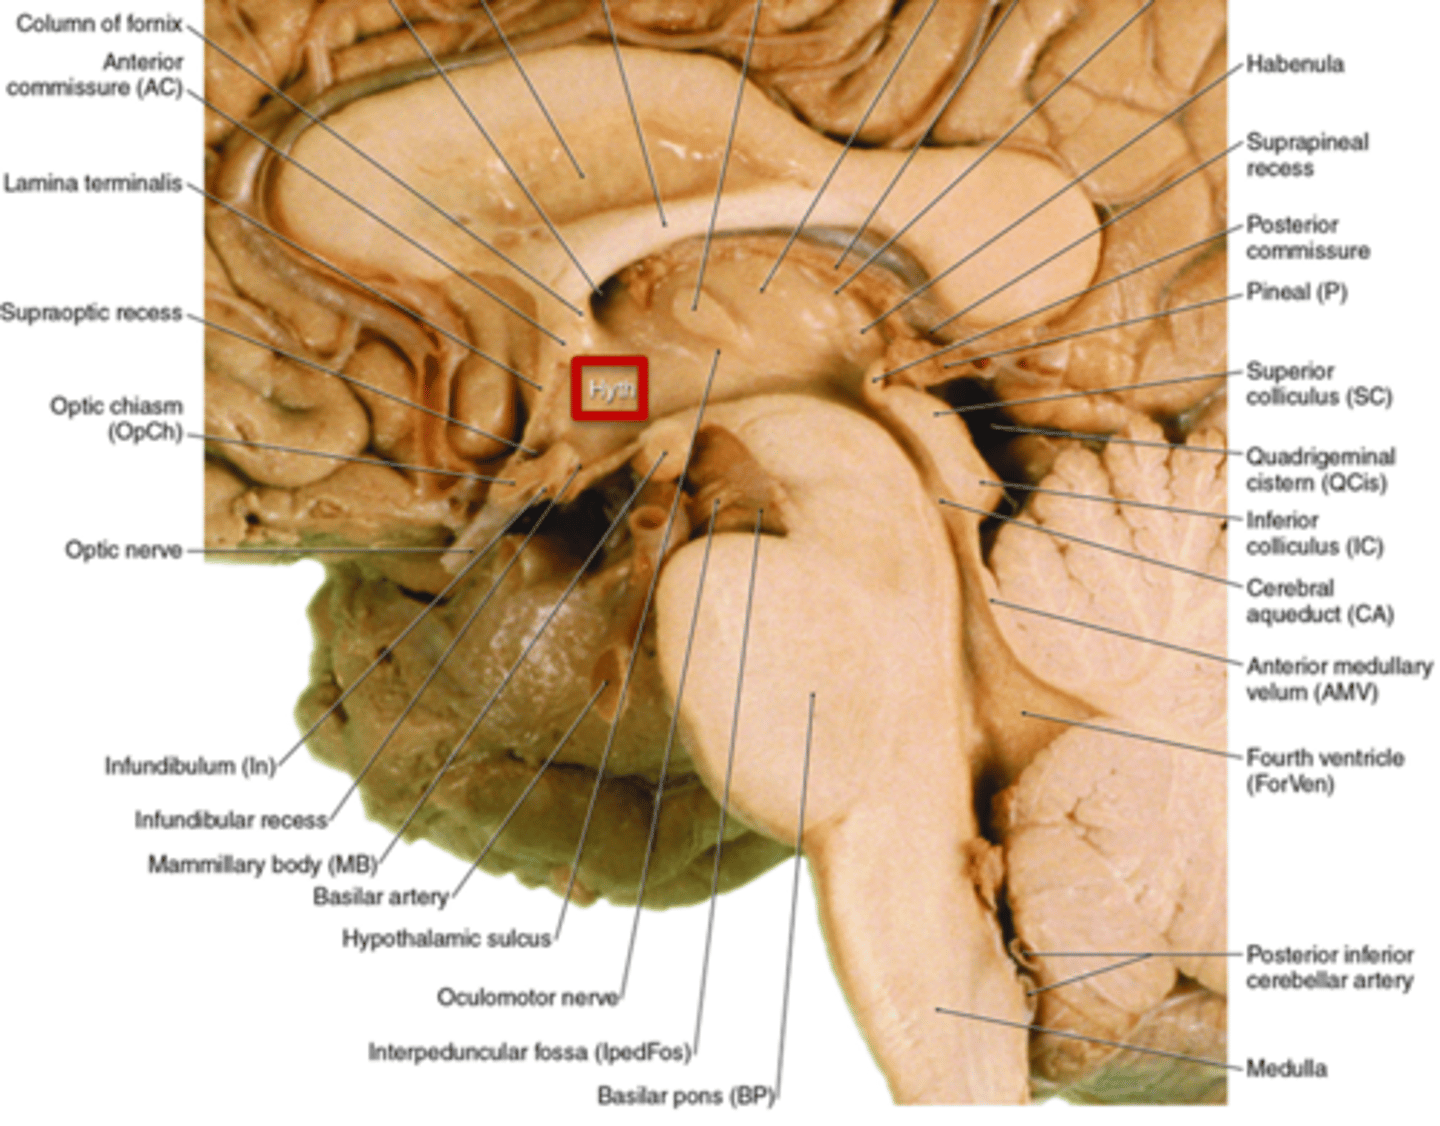

what are the 3 parts of the brainstem?

1. midbrain

2. pons

3. medulla

what are the 4 areas that the brainstem can be divided into (from posterior to anterior)?

1. tectum

2. ventricular system

3. tegmentum

4. basal portion

which area of the brainstem is the roof over the ventricular system?

tectum

which area of the brainstem makes up the core of the brainstem?

tegmentum

which area of the brainstem is situated most anteriorly?

basal portion

which region of the brainstem contains the cerebral penduncles? what is the ventral portion of the cerebral peduncles that contain corticospinal and corticobulbar fibers?

midbrain; crus cerebri

which region of the brainstem contains the cerebral aqueduct?

midbrain

what are 2 important structures of the diencephalon?

1. thalamus

2. hypothalamus

what structure of the diencephalon regulates the of flow sensory and motor information from various location that will ultimately reach the cortex?

thalamus

what structure of the diencephalon is the relay station for all but one sensory tracts on their way to the cortex? what is the exception?

thalamus

olfactory is the only tract to bypass the thalamus and go directly to the cortex

what structure of the diencephalon is the main visceral control center of the brain?

hypothalamus

what structure of the diencephalon mediates a wide range of functions through connections with endocrine, autonomic, somatic motor, limbic systems, and maintaining a state of homeostasis?

hypothalamus